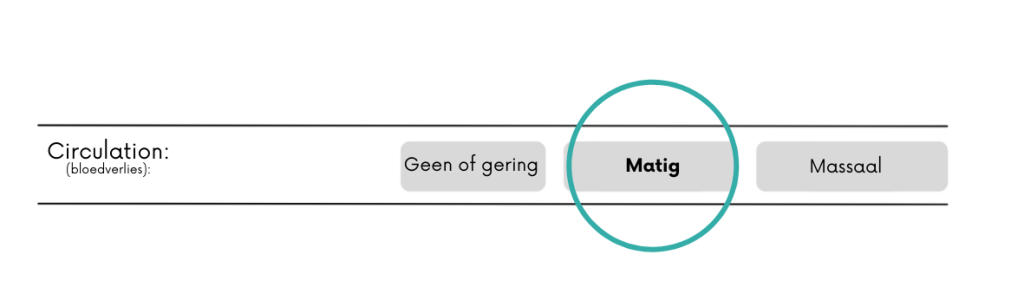

Nee/gering = geen bloeding of beetje sijpelen.

Matig = een bloeding die niet volledig onder controle is te krijgen door het uitoefenen van directe druk.

Massaal = bloed gutst met grote hoeveelheden eruit. Hieronder vallen ook grote hoeveelheden bloed braken of ophoesten.